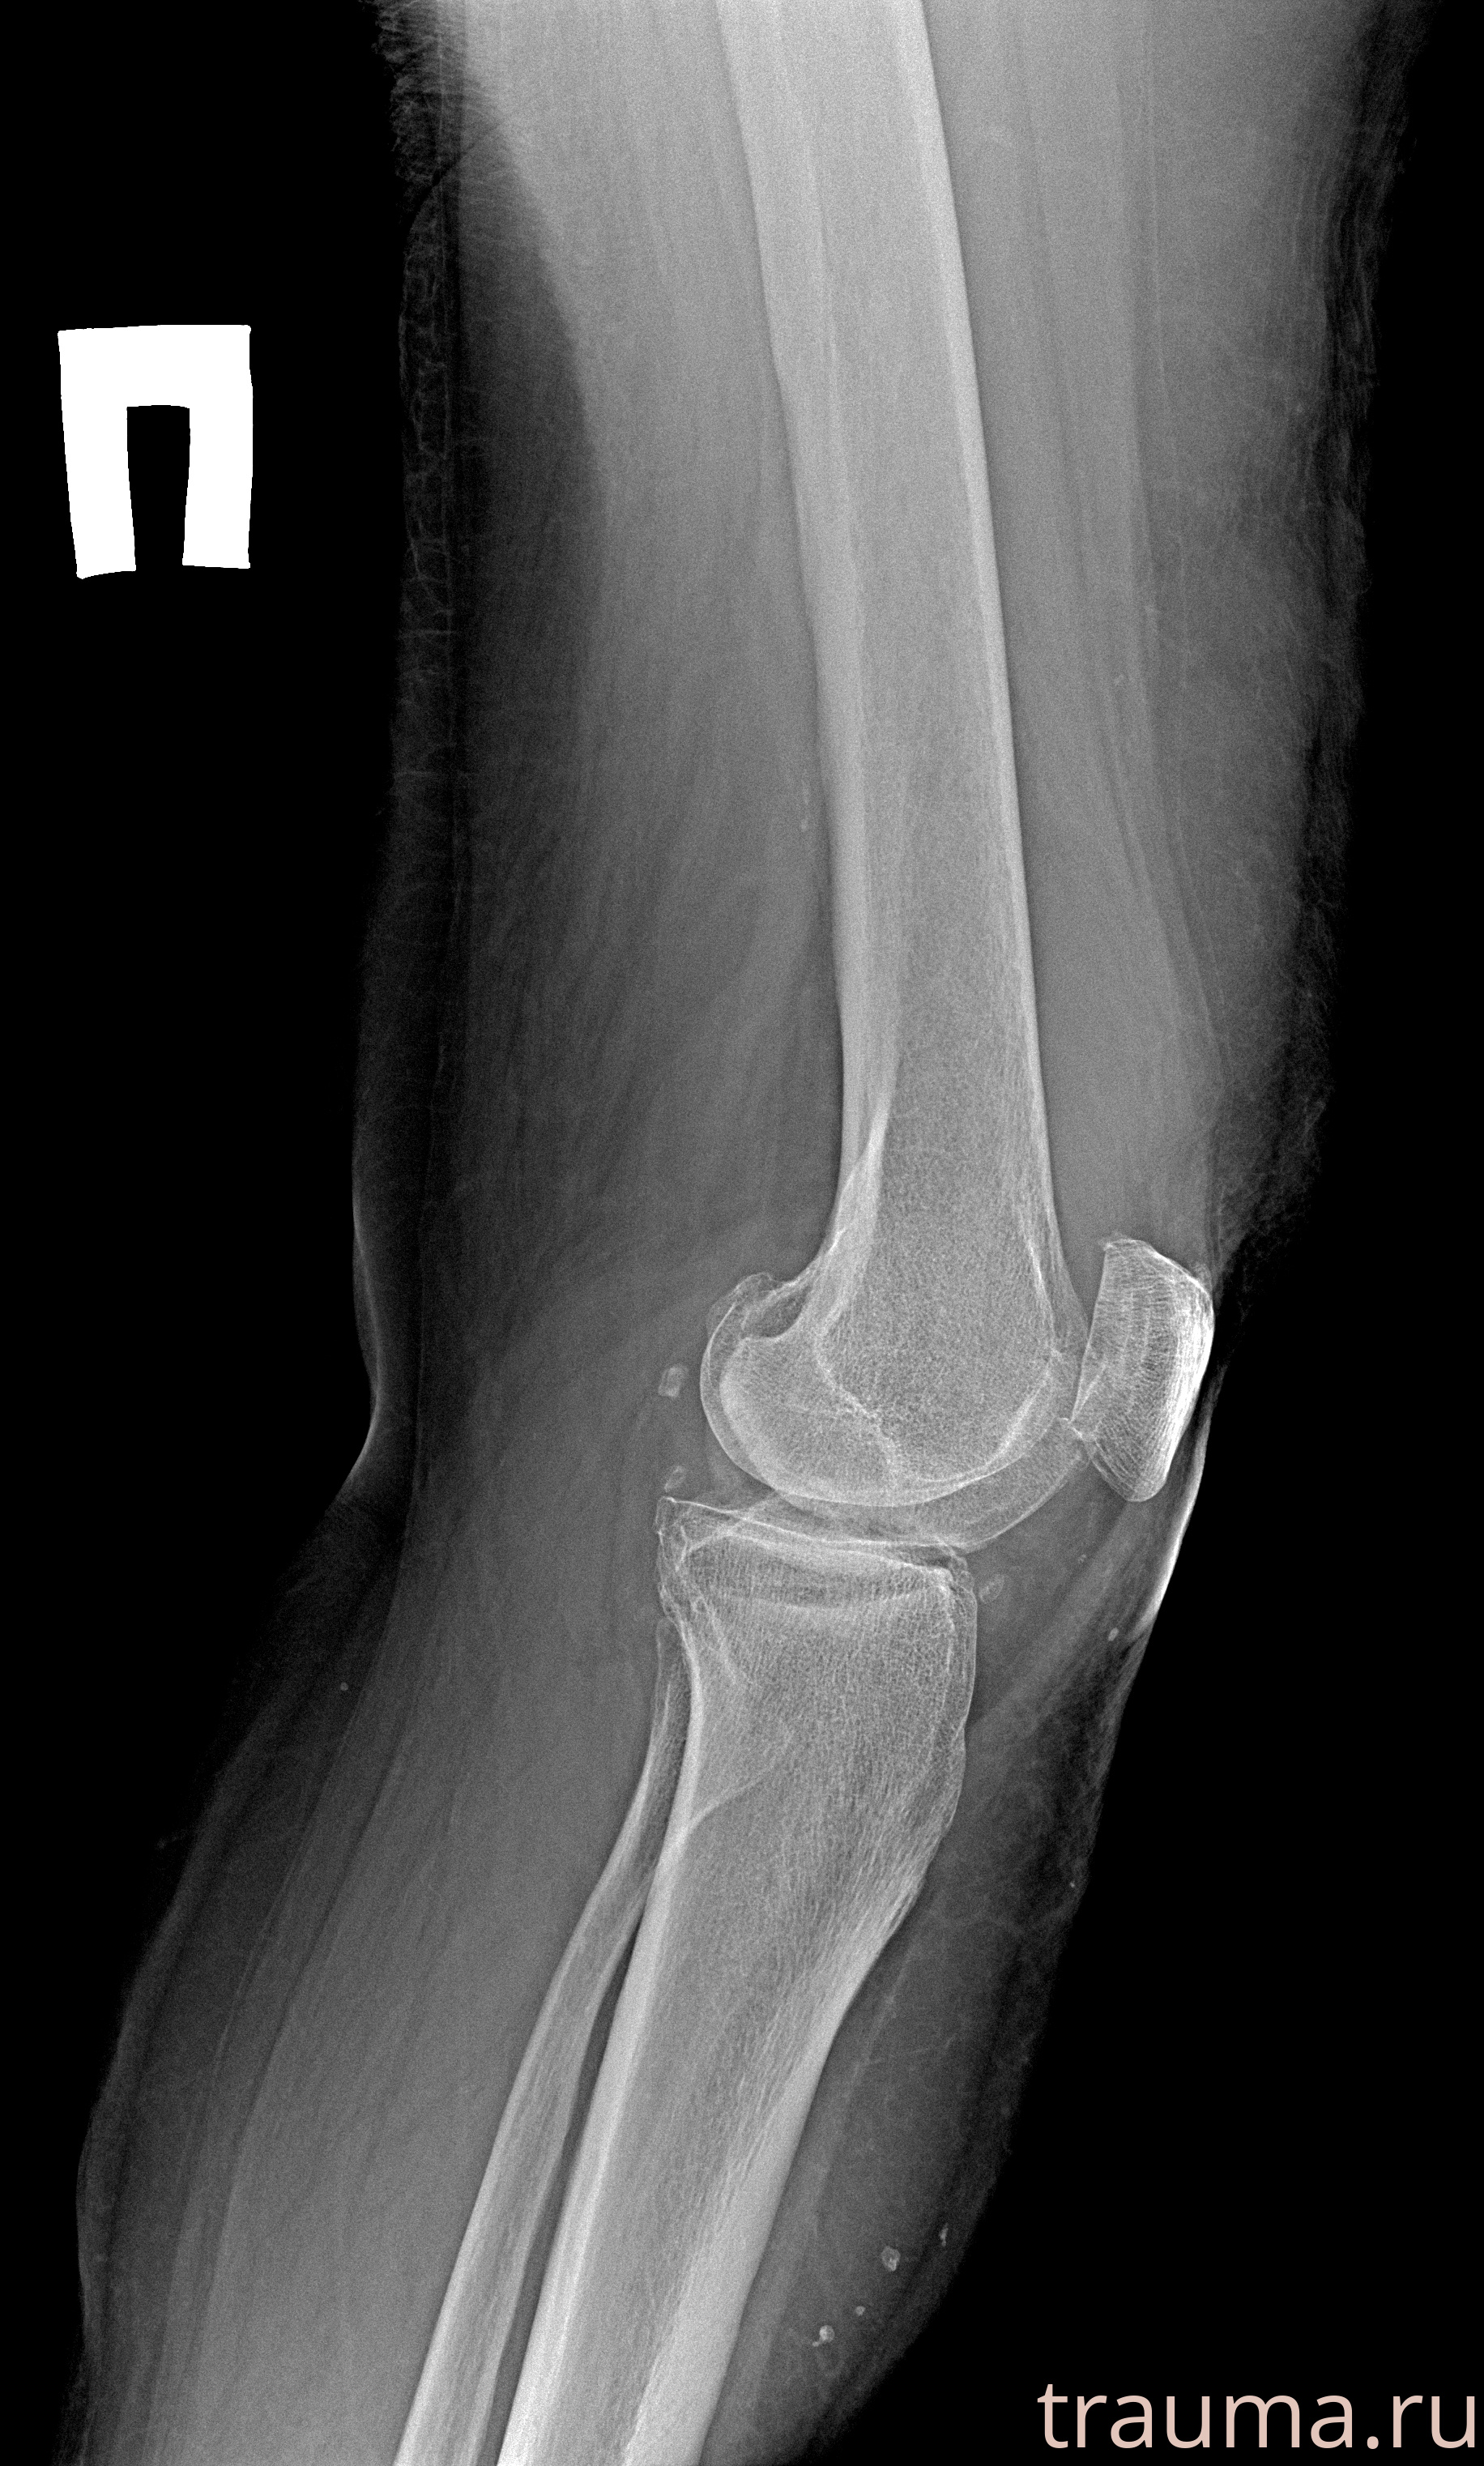

Рентген на дому: по вашему адресу приезжает врач-рентгенолог, травматолог-ортопед с мобильным рентгеновским аппаратом, проводит диагностику травмы или заболевания, делает необходимые рентгенограммы, дает рекомендации по дальнейшему лечению. Получить качественные снимки в домашних условиях возможно благодаря уникальной методике, разработанной МосРентген Центром для института  Склифосовского